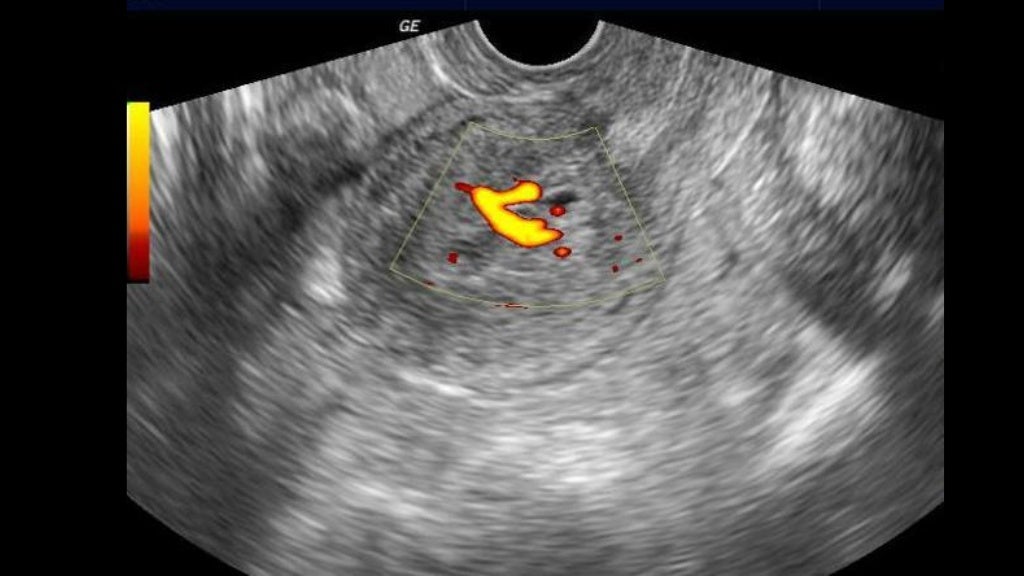

from www.researchgate.net

Ultrasound showing evidence of retained products of conception,... Download Scientific Diagram